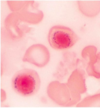

Describe.

Name.

1. spherocytes

2. hereditary spherocytosis